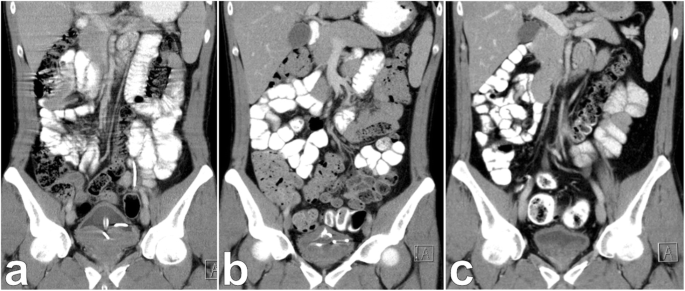

Ultimately, the diagnosis of Burkitt’s lymphoma was made 4 months after initial presentation and only 6 days later systemic chemotherapy according to the GMALL (German Multicenter Study Group for Adult Acute Lymphoblastic Leukemia) B-ALL/NHL 2002 protocol was started. It consisted of a total of 6 cycles of 3 different drug regimen including dexamethasone, cyclophosphamide, rituximab, dexamethasone, vincristine, ifosfamide, etoposide, cytarabine and high-dose methotrexate. Concurrent medication was composed of acyclovir, trimethoprim/sulfamethoxazole, ciprofloxacin, pantoprazole, G-CSF, amphotericin B mouth rinse and Glandomed® mouthrinse. The first cycle was given as a milder regimen with dexamethasone and cyclophosphamide together with hydration, allopurinol and urinary alkalization in order to prevent tumor lysis syndrome. Nonetheless, the patient developed neutropenic fever and grade 4 mucositis and required extensive analgesic and antibiotic treatment. Due to increasing abdominal pain a CT scan was done which excluded a tumor lysis with gastric perforation. It rather showed a response to treatment according to Lugano treatment response criteria (Fig. 4) [14].

Regression of prostatic Burkitt’s lymphoma during chemotherapy. Coronal view of contrast enhanced CT scan showing prostatic Burkitt’s lymphoma before (a), during (b) and after (c) chemotherapy. Burkitt’s lymphoma caused urinary retention and bilateral hydronephrosis. a Foley catheter and ureteral stents were inserted and chemotherapy started. b After one of 6 cycles significant downsizing of the lymphoma was seen. c Foley catheter and ureteral stents could be removed after 6 cycles of chemotherapy

During the following cycles there was one more episode of neutropenic fever. Mucositis persisted only on a lower level. The Foley catheter was removed 2 months after initiation of chemotherapy. Hereafter satisfactory voiding with insignificant post-void residual volume was established. After finishing chemotherapy, a CT scan showed complete response. Following this, both ureteral stents were removed. Subsequent sonography of the kidneys could exclude persisting hydronephrosis. Another CT scan 3 months later confirmed complete remission of Burkitt’s lymphoma (Fig. 4c). The patient recovered completely and is now participating in follow-up care.